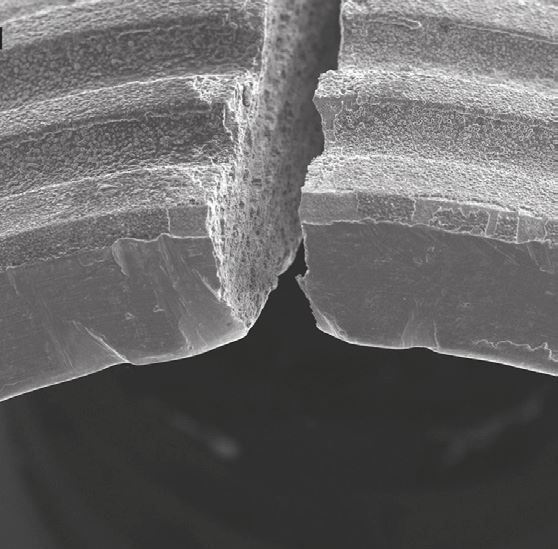

Соединение коронки и имплантата через индивидуальный абатмент

Важнейшая часть в протезировании на имплантатах, от которой зависит срок службы импланта. Именно на абатмент приходится вся жевательная нагрузка на протяжении всего срока службы ваших новых зубов. Он находится в самой опасной зоне подверженной скоплению бактерий и от его качеств и технологии крепления зависит надежность и долговечность конструкции. Малейшее отклонение от стандартов производителя приводит к росту зазоров и развития в них патогенной флоры или физическому повреждению имплантата.

Тип и точность соединения

Самые лучшие импланты имеют уникальное соединение с зазорами в несколько микрон. Такое соединение не допускает увеличения люфта и развития в ней бактериальной среды.

Только оригиналы

На рынке присутствуют не оригинальные решения. Их применение помогает съэкономить в краткосрочном моменте, но в долгосрочной перспективе, их применение подвергает пациента риску облома имплантата или развития патогенной среды в зазорах.